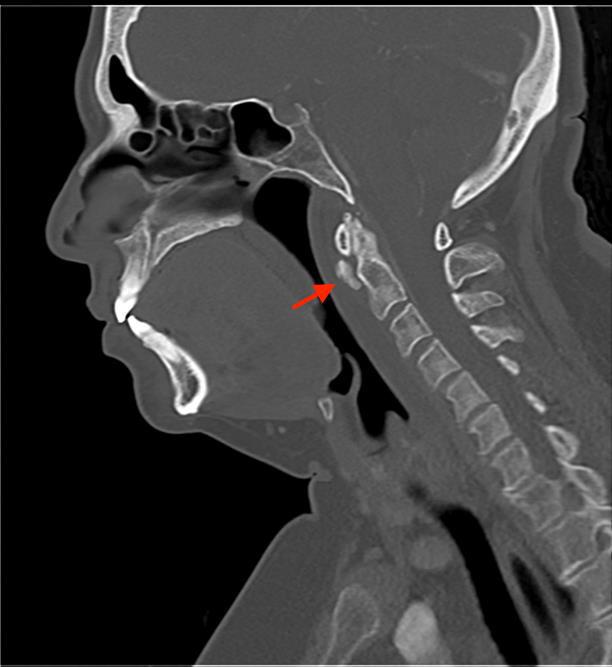

Laboratory results showed white blood cell count (WBC) of 11.59 x 109 cells per liter (x 109/L) (reference range: 4.50 – 11.0 x 109/L). Erythrocyte sedimentation rate and C-reactive protein were not sent. Computed tomography (CT) of the neck with intravenous (IV) contrast was done, as the differential diagnosis included mastoiditis, retropharyngeal abscess, and other deep space neck infection. Computed tomography results showed prominent amorphous calcification inferior to the anterior arch of the first cervical vertebrae, highly suggestive of calcific tendonitis of the longus colli muscle (Image 1), with diffuse retropharyngeal edema (Image 2).

The characteristic CT findings include calcific deposits in the prevertebral space, ventral to the first and second cervical vertebrae, localized to the longus colli muscle. Computed tomography often will also show surrounding edema in the prevertebral or retropharyngeal space.1-3,7,9-12 Retropharyngeal effusion without surrounding structural enhancement has also been described, with the lack of an enhancing wall differentiating this fluid collection from abscess.7,9